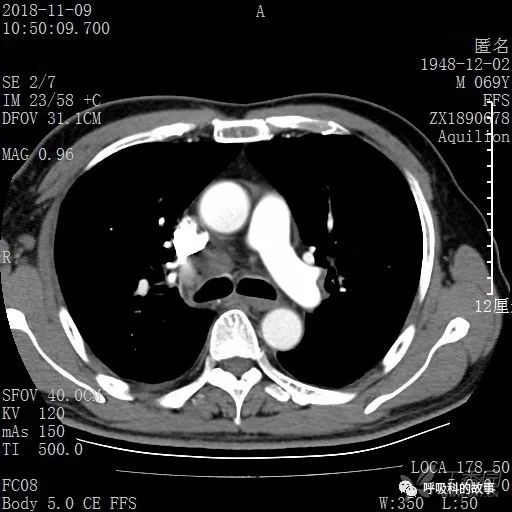

胸部增强CT示右肺门占位伴远端阻塞性肺炎,纵膈、右肺门、右侧颈根部、右侧腋下及肝门部肿大淋巴结。两侧胸腔少量积液。

纵隔窗的增强CT

肺窗CT